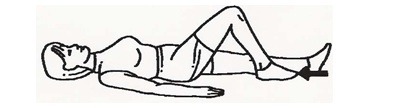

به پشت دراز بکشید یا بنشینید، خم شوید و مچ پا را به سرعت صاف کنید. این حرکت را 20 بار تکرار کنید. این تمرین برای جلوگیری از تشکیل لختههای خون مفید است.

به پشت دراز بکشید، پا را خم و راست کنید. این حرکت را 10 بار تکرار کنید. بروز اندکی درد در ابتدای این تمرین طبیعی است، اما حتماً مطمئن شوید که آسیبی به جراحت زانو وارد نمیشود.